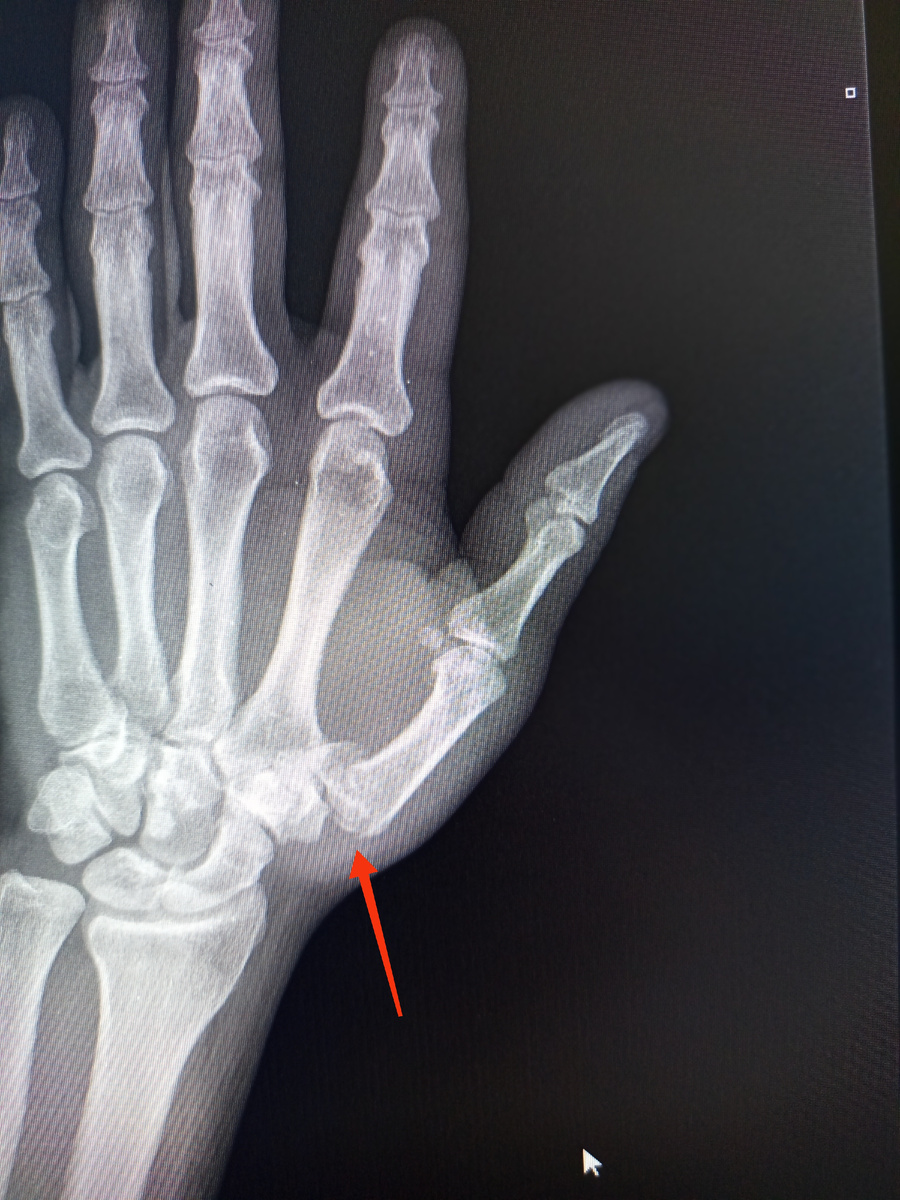

Парень , 19 лет , пришел и принёс бумажную копию снимков. Травма от 17 числа , упал с самоката.

Как не беспокоило? Да еще и рука правая. Там срастаться все начало уже.

Костные отломки нужно сразу сопоставлять , а не ждать пока сами начнут срастаться , и только потом идти к врачу.